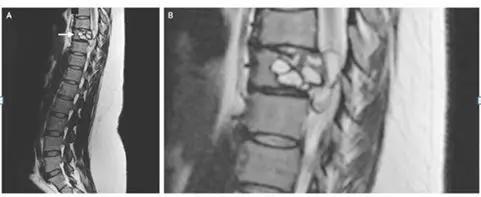

女子脊椎中发现寄生虫

Credit: The New England Journal of Medicine

一名法国妇女称其腿部会出现“电击”的感觉,经检查发现,她患有一种罕见的感染——脊椎里潜伏着绦虫幼虫。

这名女性背部的核磁共振显示,其脊柱有一处病变,需要手术切除。进一步的测试显示,这种病变是由细粒棘球绦虫感染引起的,这是一种小型绦虫,常见于狗和一些农场动物(绵羊、牛、山羊和猪等)。

这种绦虫可引起一种叫做包虫病的疾病,在这种疾病中,幼虫会形成囊肿,并在人体内缓慢生长。这种疾病在法国很少见,研究人员尚不清楚这位妇女是如何感染的。据报道,她曾接触过马和牛等农场动物。研究人员还怀疑,可能是吃了被寄生虫污染的蔬菜导致。在接受了一种抗寄生虫药9个月后,该妇女残留症状消失。

7月11日,《NEJM》杂志发表了该病例的报告。